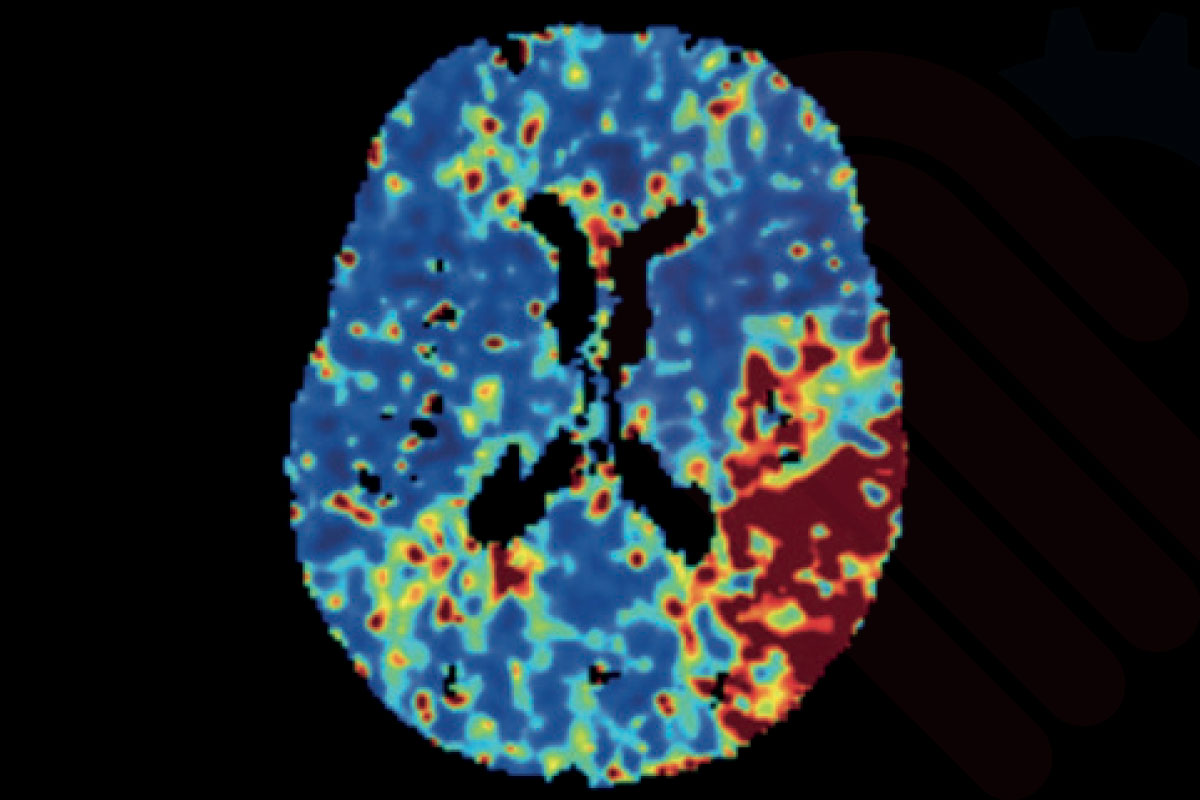

SVD tabanlı perfüzyon haritaları (CBF, CBV, MTT, Tmax)

Cercare Medical Neurosuite Stroke yazılımı, CT ve MR perfüzyon verilerini kullanarak SVD (Singular Value Decomposition) tabanlı analiz gerçekleştirir. Bu yöntemle beyin kan akımı (CBF), beyin kan hacmi (CBV), ortalama geçiş zamanı (MTT), zaman-gecikmesi (Tmax), maksimum yoğunluk projeksiyonu (MaxIP) ve tepe zamanı (TTP) parametreleri güvenilir biçimde hesaplanır.

Bu parametreler, iskemik inme vakalarında penumbra (kurtarılabilir doku) ile çekirdek infarkt (geri dönüşsüz doku) ayrımını netleştirmede kritik rol oynar. Özellikle Tmax > 6 sn ve düşük CBF değerlerinin birlikte değerlendirilmesi, infarkt çekirdeğini yüksek doğrulukla tanımlarken; CBV ve MTT haritaları penumbra bölgesinin belirlenmesinde önemli katkı sağlar*.

Klinik çalışmalar, bu analiz yaklaşımının hasta seçiminde doğruluğu artırdığını ve tedavi penceresinin uzatılmasına katkı sunduğunu göstermektedir*. Böylece hekimler, tromboliz veya trombektomi gibi tedavi seçeneklerini çok daha hızlı ve güvenilir biçimde planlayabilir.